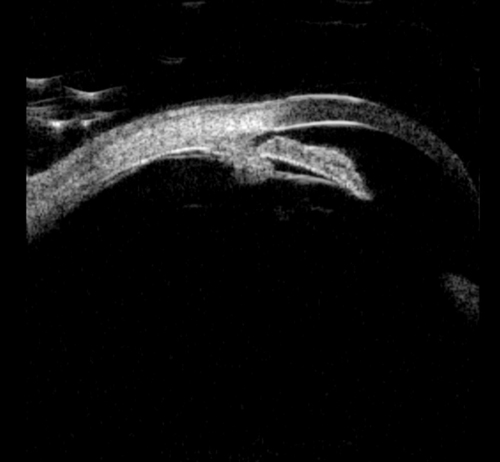

Figure 2a: Plateau iris. Sectoral UBM images in photopic conditions showing flat iris plane,

deep central PAC, anteriorly positioned ciliary sulcus, and angular iris root.

Figure 2b: Plateau iris - dark adaptation showing irido trabecular contact.

The diagnosis of plateau iris can be made by UBM and is characterised by: an angular iris root which is steeply rising combined with a flat iris plane and anterior rotation of the ciliary body (or processes). Indeed, UBM has indicated that plateau iris is more common than previously thought, and occurs in at least 50% of PAC(G) cases. UBM has been shown to identify patients with intermittent angle closure previously diagnosed as open angle glaucoma.